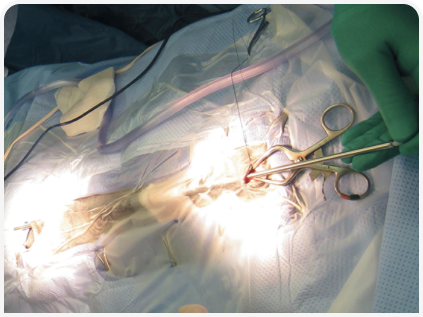

Радикальная терапия заключается в проведении хирургической операции по вентрикулоперитонеальному шунтированию.